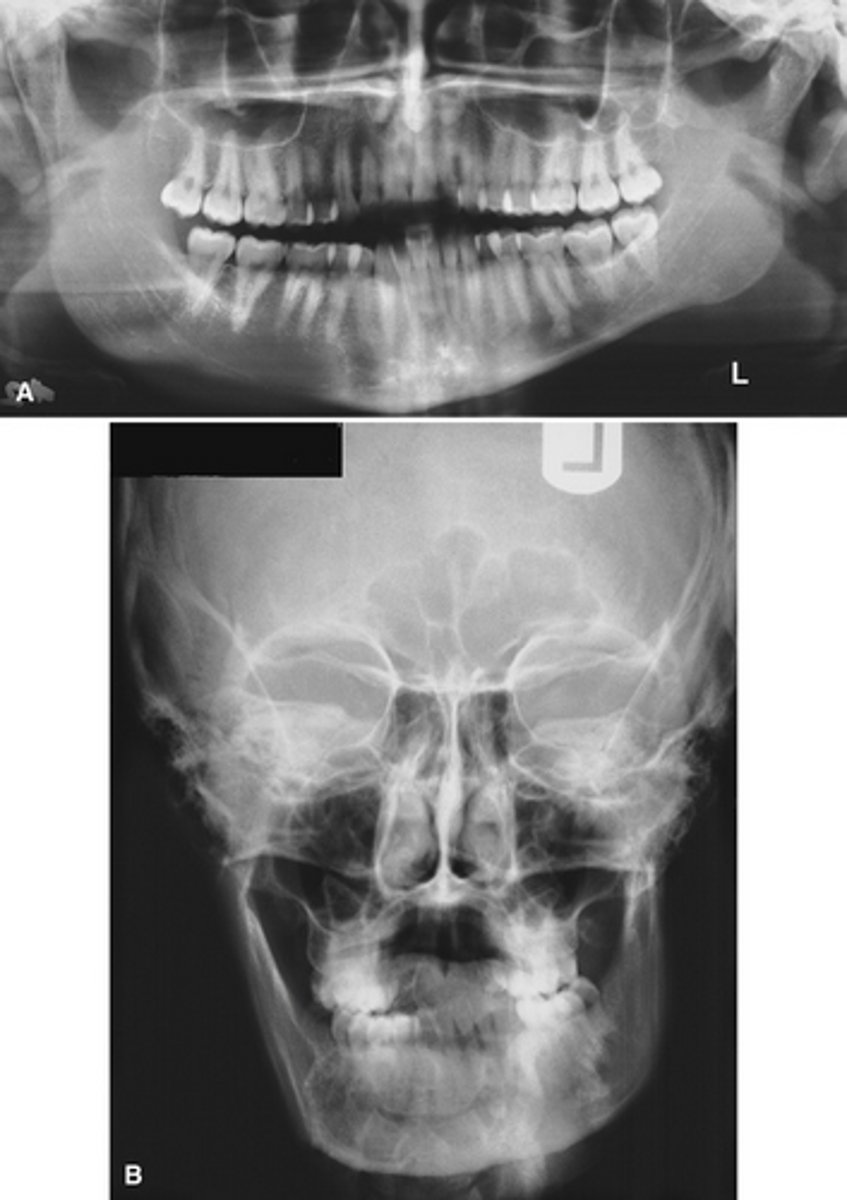

Image A shows a lateral ceph where the patient has a steep mandibular plane and anterior open bite.

Image B shows erosion of the temporal component of the TMJ

What is the diagnosis of the patient based off these radiographs and what are the features?